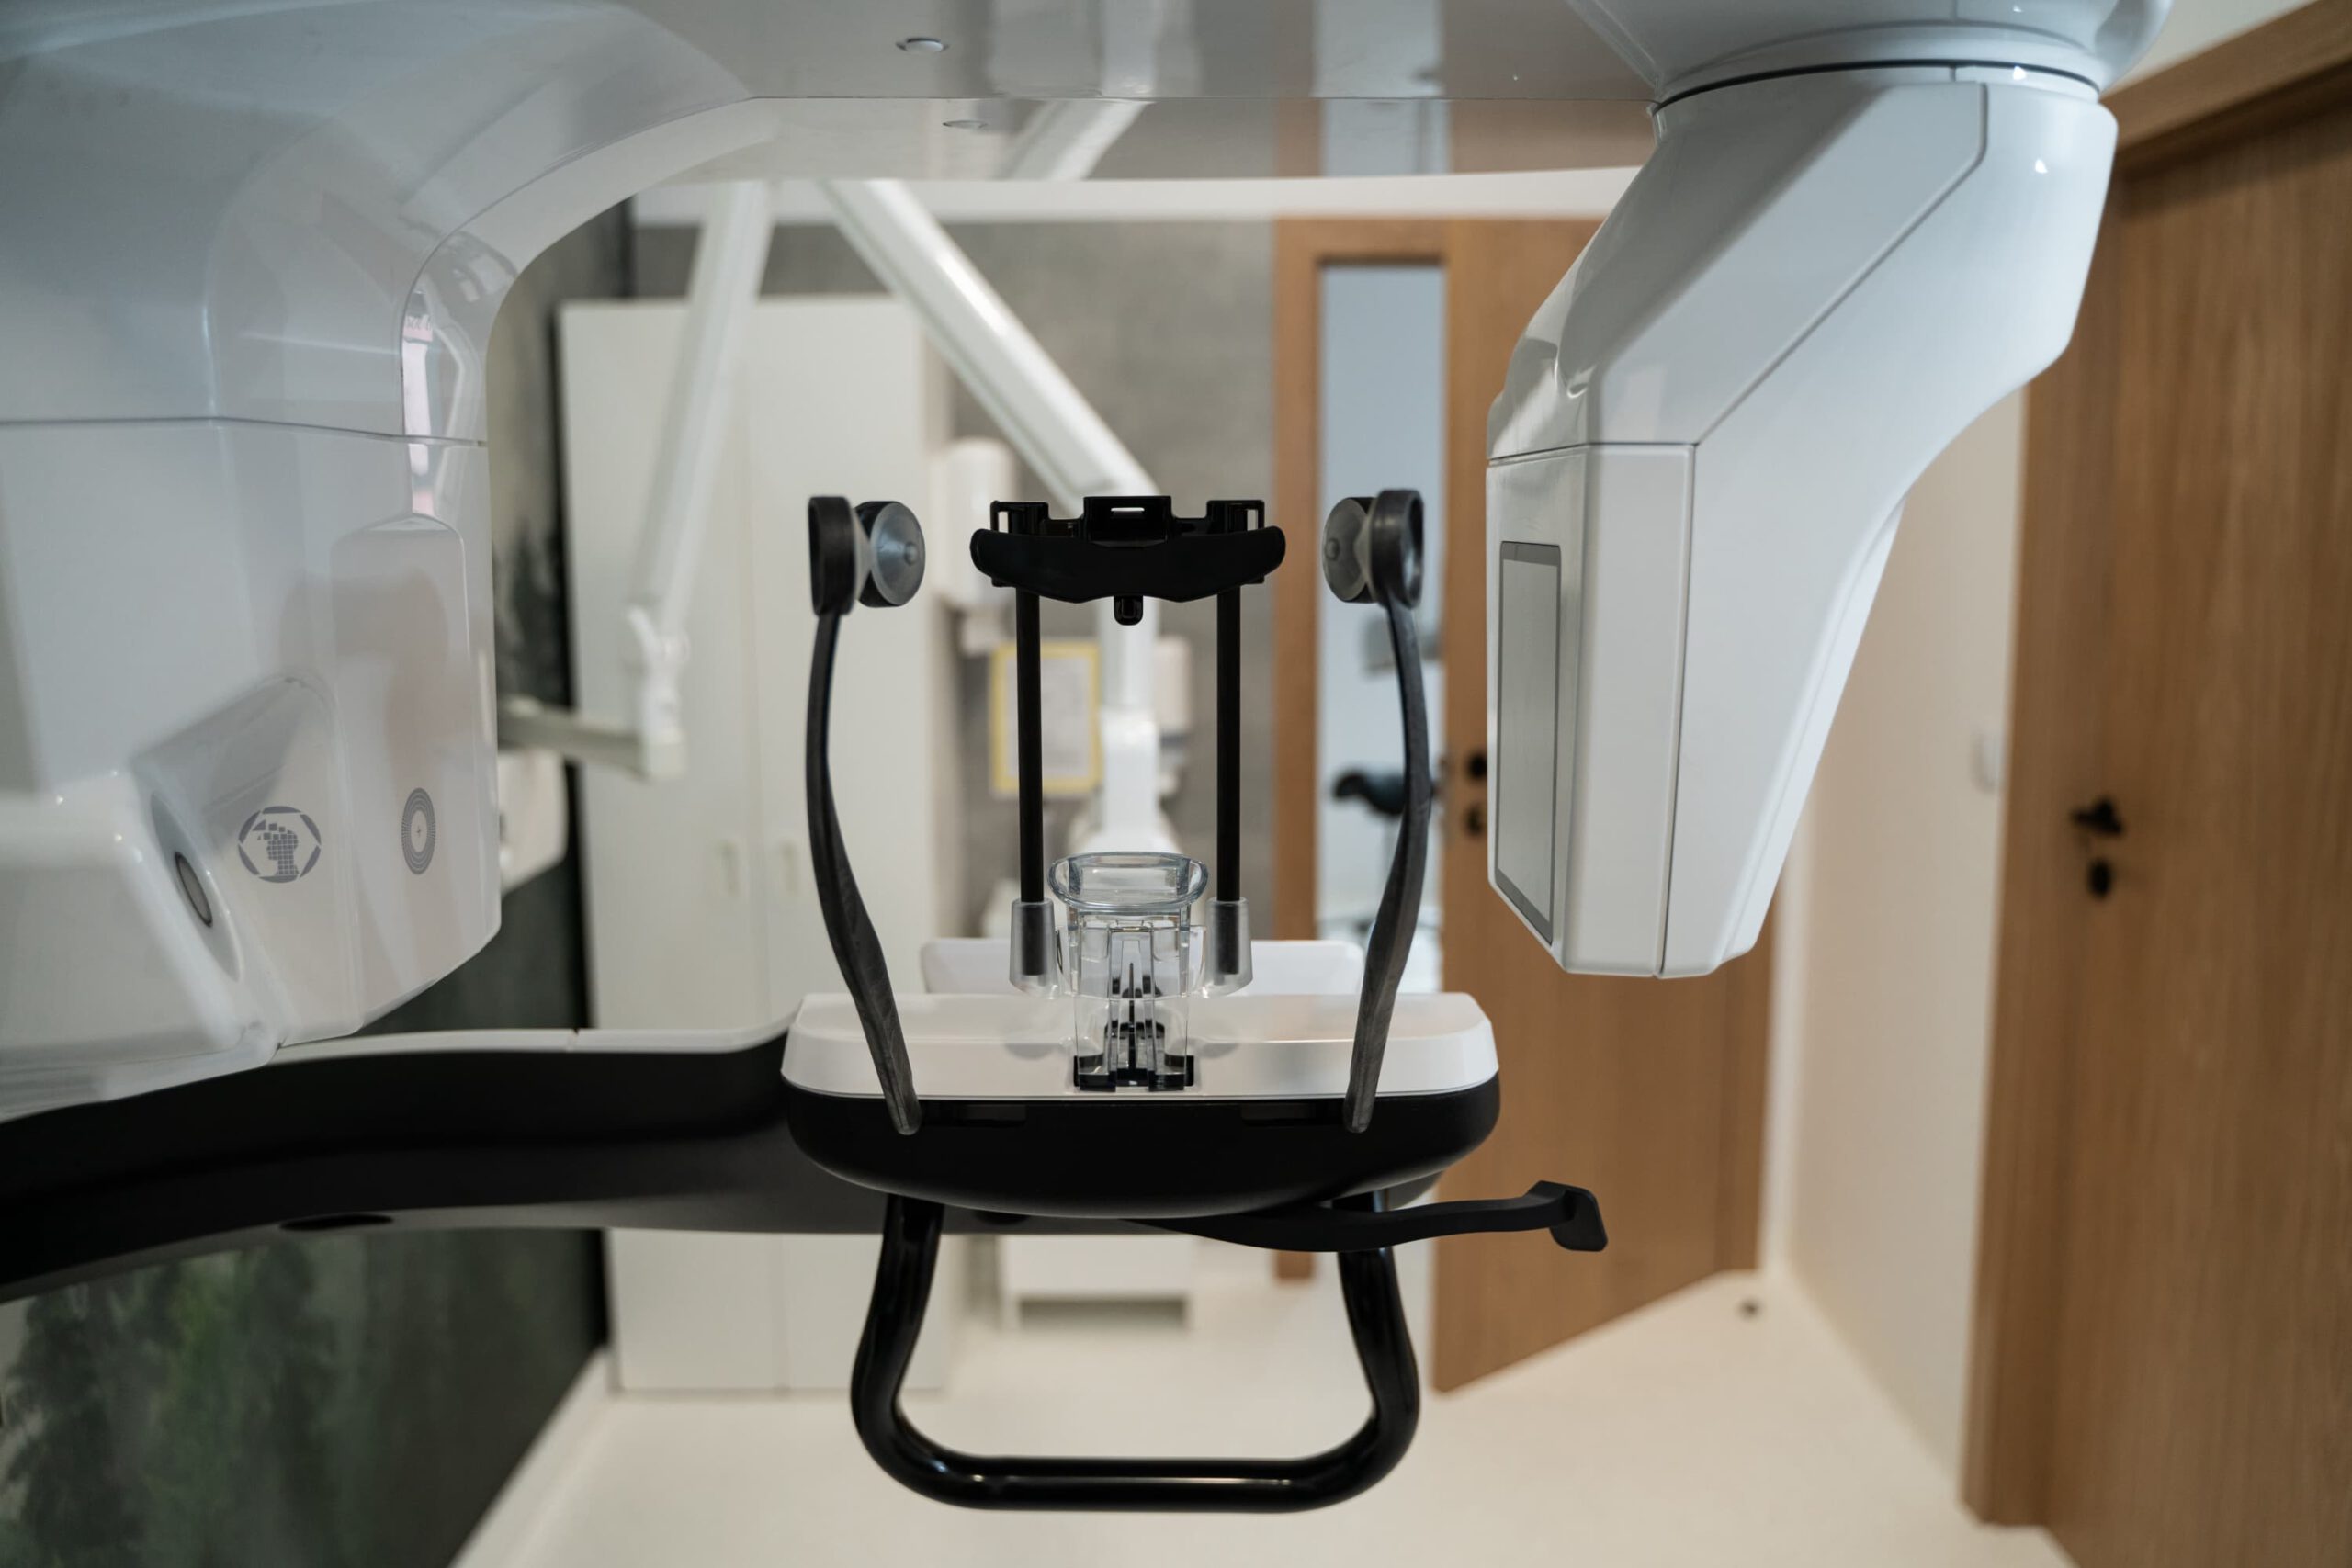

Tomograf Kodak Carestream CS 9600 jest to system, który zapewnia najwyższą dostępną jakość uzyskiwanych obrazów oraz aż czternaście różnych pól obrazowania. Zastosowane w nim innowacyjne rozwiązania pozwoliły na osiągnięcie doskonałych efektów, przy jednoczesny zwiększeniu bezpieczeństwa użytkowania. Dzięki licznym funkcjom sprawdza się jako urządzenie diagnostyczne w wielu dziedzinach stomatologii. Tomografia wykonana przy jego użyciu jest przy tym wyjątkowo dokładna. Oznacza to, że podczas badania można bardzo precyzyjnie zobrazować wszystkie tkanki organizmu – to pozwala na szybkie postawienie jednoznacznej diagnozy oraz natychmiastowe wdrożenie odpowiednich metod leczenia.

Tomograf Kodak Carestream CS 9600 jest to system, który zapewnia najwyższą dostępną jakość uzyskiwanych obrazów oraz aż czternaście różnych pól obrazowania. Zastosowane w nim innowacyjne rozwiązania pozwoliły na osiągnięcie doskonałych efektów, przy jednoczesny zwiększeniu bezpieczeństwa użytkowania. Dzięki licznym funkcjom sprawdza się jako urządzenie diagnostyczne w wielu dziedzinach stomatologii. Tomografia wykonana przy jego użyciu jest przy tym wyjątkowo dokładna. Oznacza to, że podczas badania można bardzo precyzyjnie zobrazować wszystkie tkanki organizmu – to pozwala na szybkie postawienie jednoznacznej diagnozy oraz natychmiastowe wdrożenie odpowiednich metod leczenia.